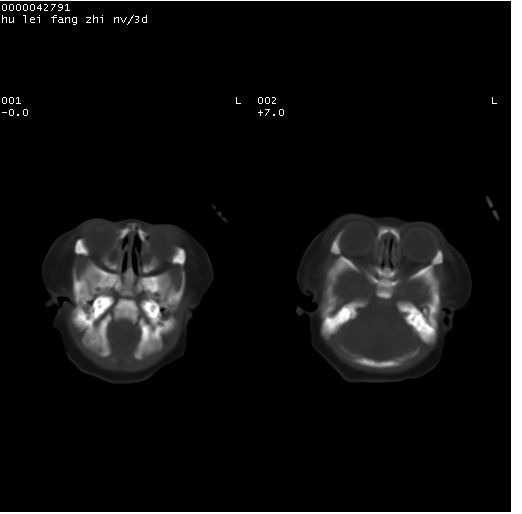

患儿 女,3天。惊跳,纳差。第二胎顺产,羊水ⅱ度。

临床诊断:hie?

颅脑ct轴位平扫(层厚、层距均为7mm),图像如下:

hie合并蛛网膜下腔出血

hie合并蛛网膜下腔出血,五、六脑室形成。

支持hie伴少量蛛血.

支持胼胝体发育不良。

支持hie,胼胝体发育差些

支持胼胝体发育不良